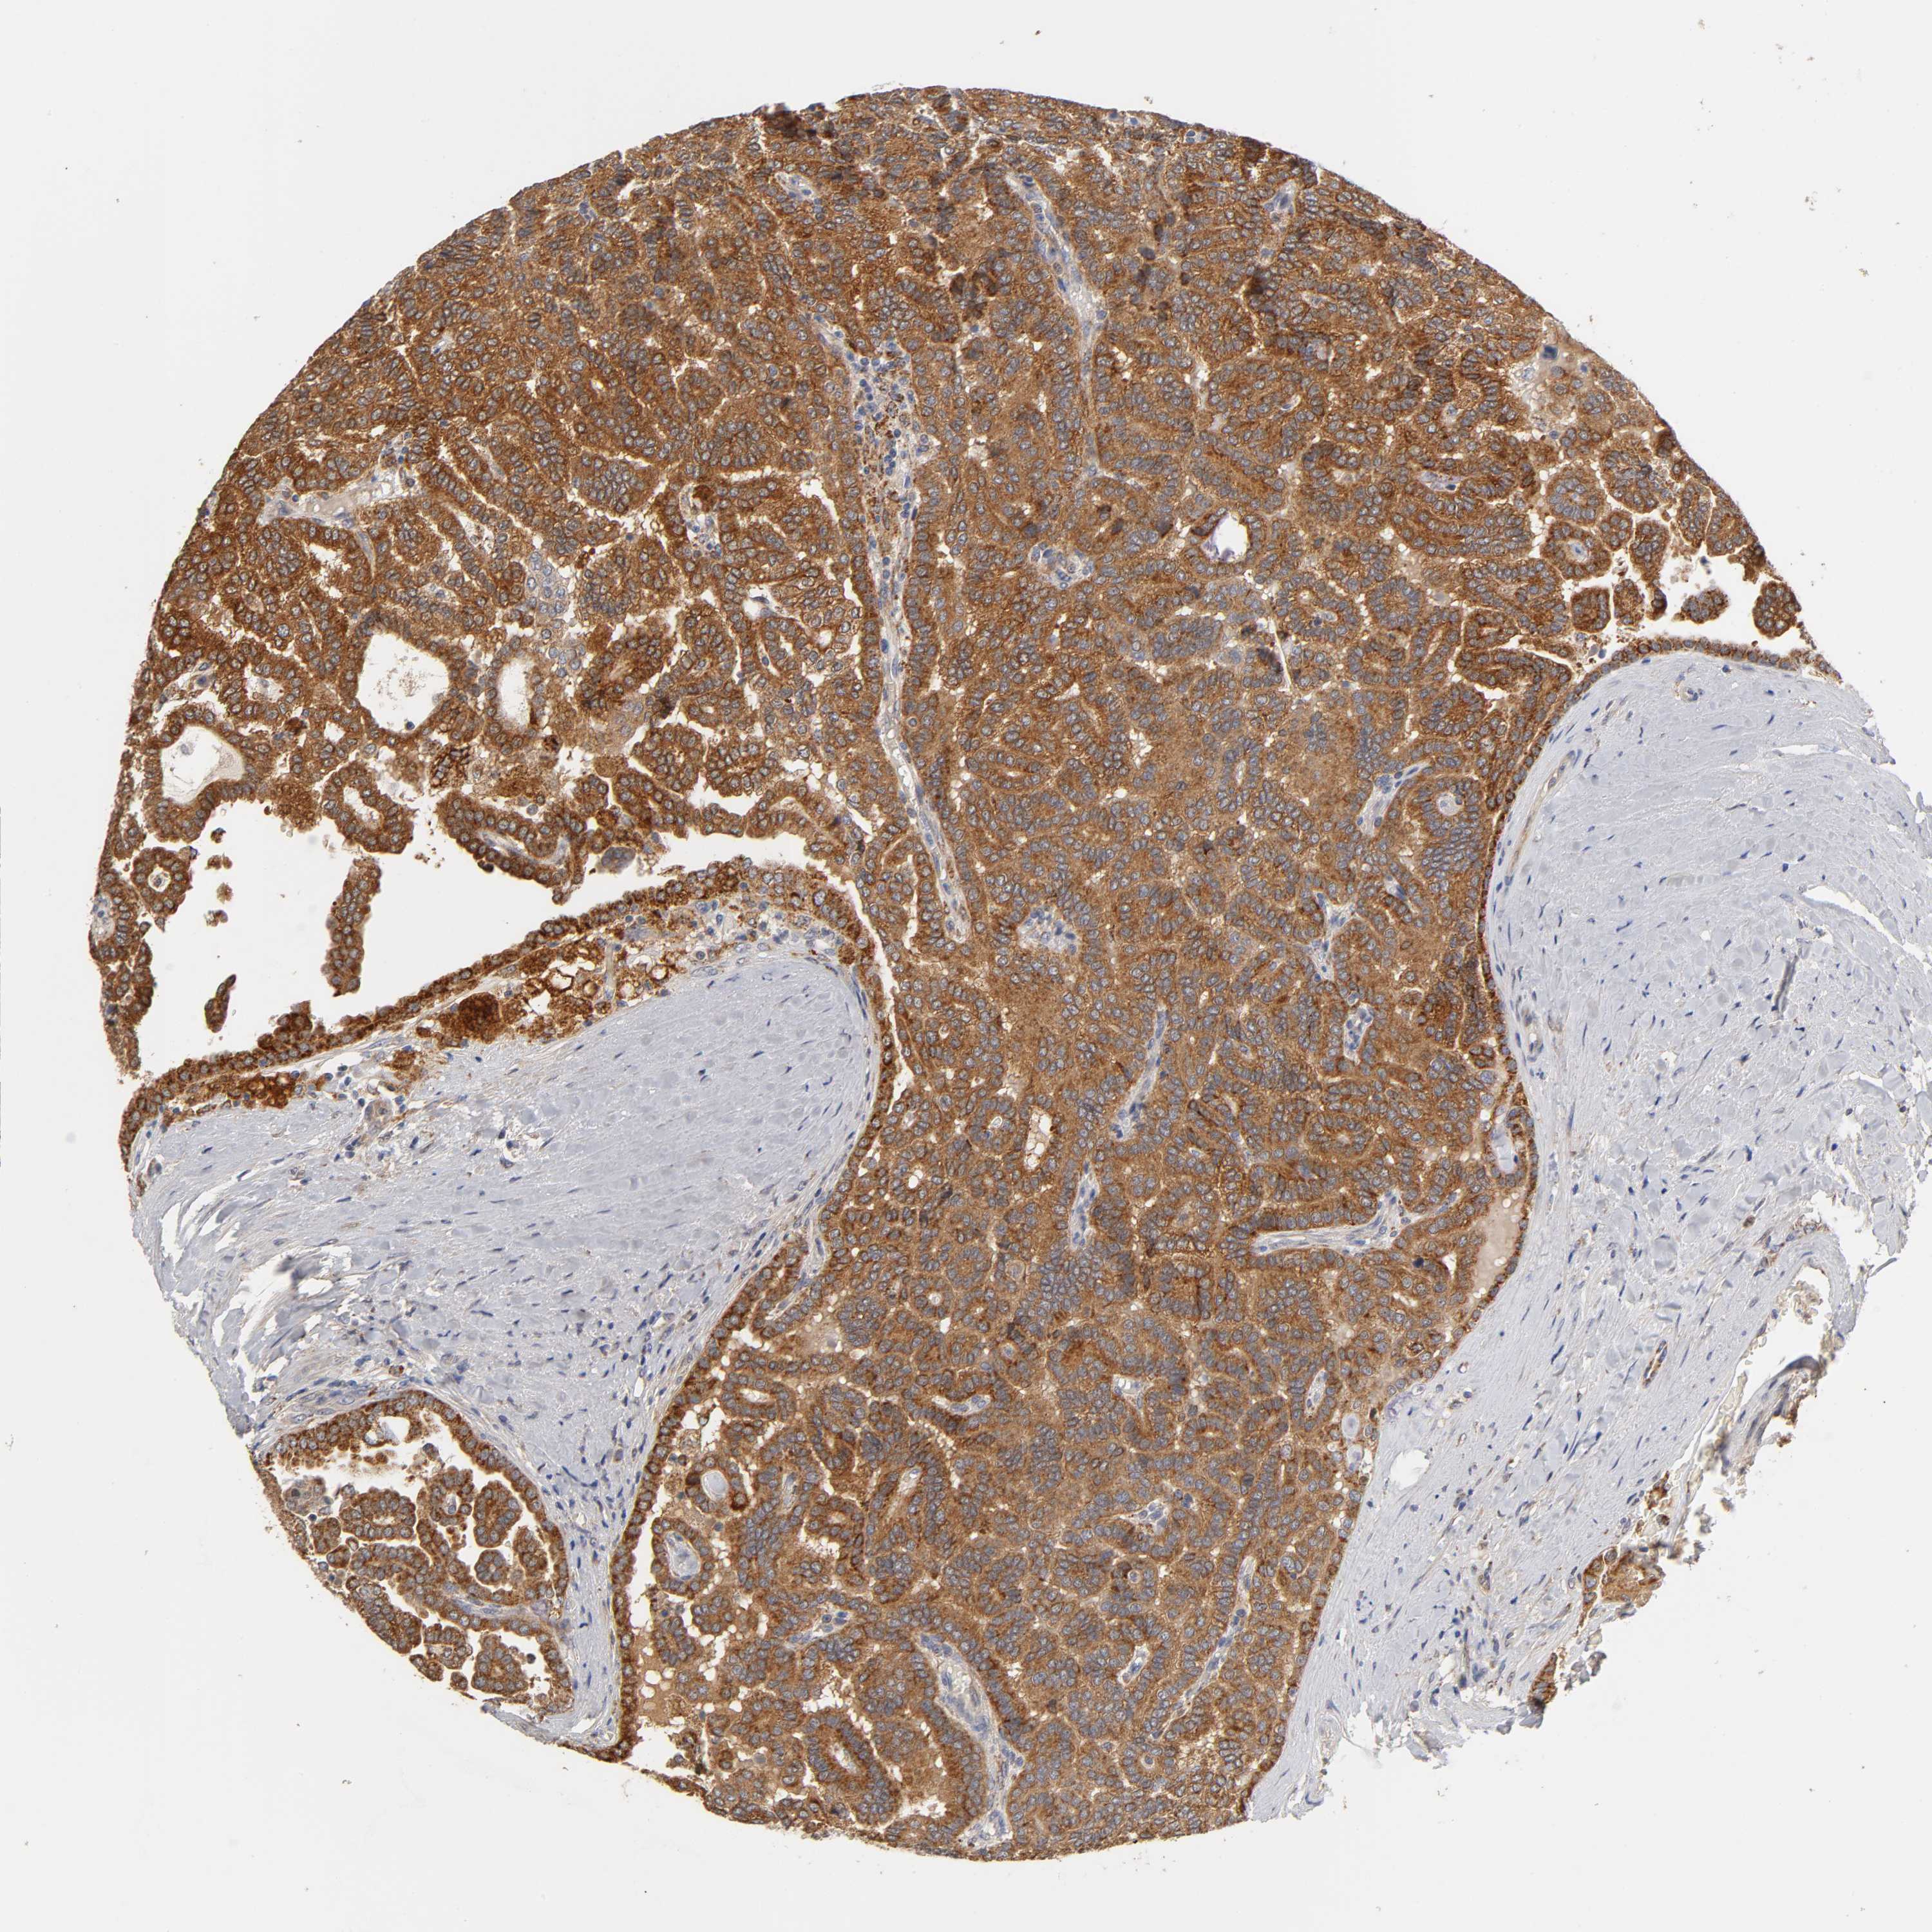

CANCER RENAL CANCER Show tissue menu

KICH TCGA KIRC TCGA KIRC VALIDATION KIRP TCGA PROTEIN RCC CPTAC PROTEIN EXPRESSION